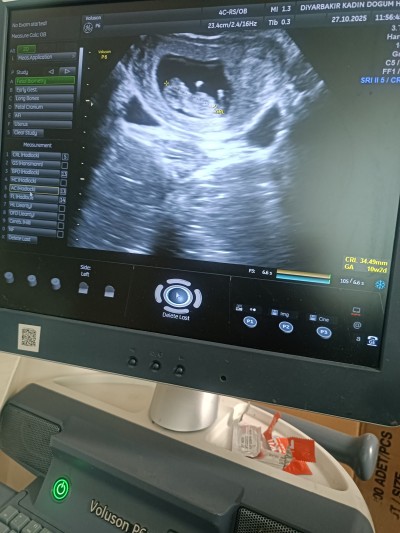

12+3 gebeyim cinsiyet nub teorsini bilenler yardımcı olablr mi ? Merak ediyorum da biliyorum erken ama merak duygusu var

Gebelik haftası 12+3

Nub çıkıntısı kız gibi duruyor ama hayırlısı olsun tabiki